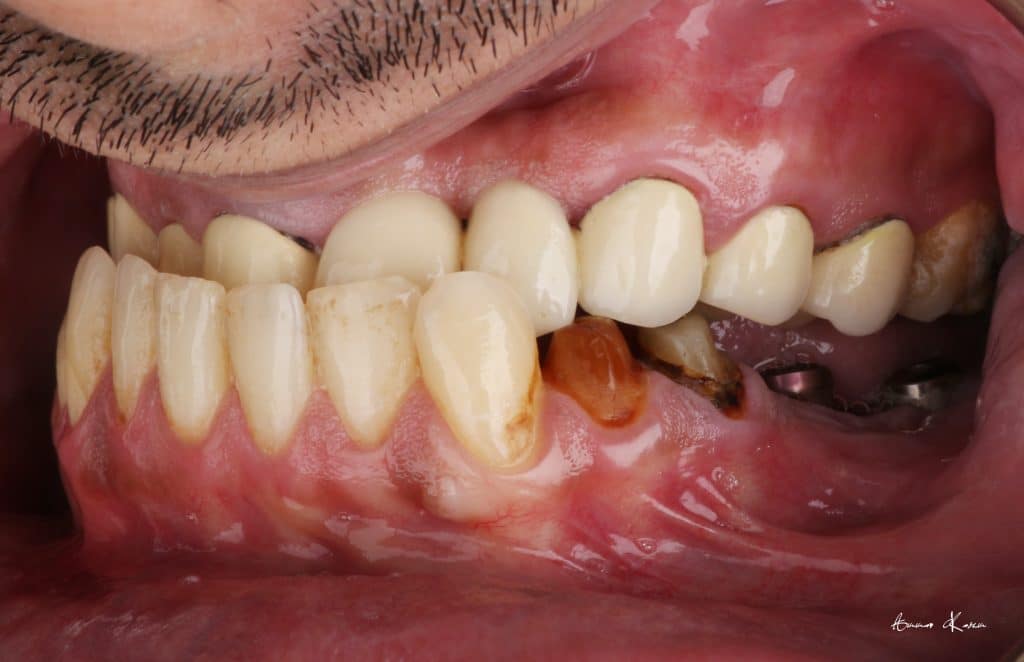

35 years old male patient having old PFM restorations

The patient was normally class I occlusion type ( according to old photos and cephalometric analysis) till he received this defective restorations 10 years ago

1- Removal of old restorations

2- Restorative phase ( including RCT, post and core )

3- Deprogramming to release stresses and to adjust the new occlusion

4- Facebow records and mounting on semi adjustable articulator

Temporization phase including;

5- 1st mock up ( edge to edge ) for 2 months

6- 2nd mock up ( Normal class I) for 3 months